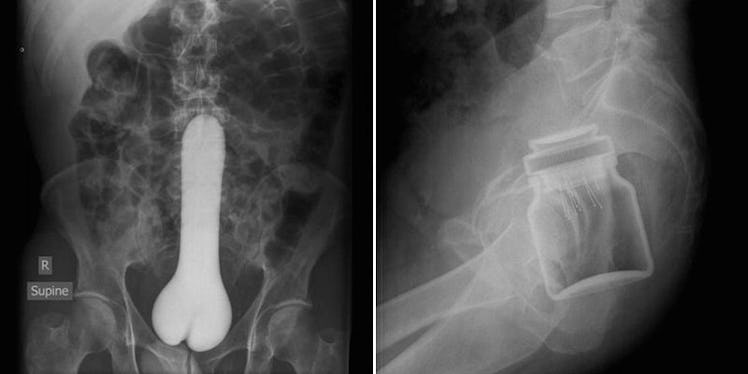

Website Compiles X-Ray Photos Of Weird Things Stuck Up People's Butts

Gizmodo turned me on to Radiopedia, which features a number of x-rays of various diseases and injuries submitted by doctors around the world, and yes, they do have a section devoted exclusively to scans of stuff stuck inside people's butts (or "rectal foreign bodies" if we're being professional).

These are the best cautionary tales.